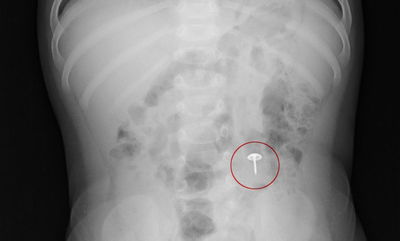

נס רפואי: בתו של מתנדב 'איחוד הצלה' מביתר עילית בלעה מסמר ממשחק ילדים, חבריו לארגון העניקו לה טיפול ראשוני. בצילום רנטגן בבית החולים, המסמר נראה ונקבע תאריך לניתוח, אך רגע לפני, באורח נס, יצא המסמר באופן טבעי מבלי לגרום חלילה לנזק לילדה